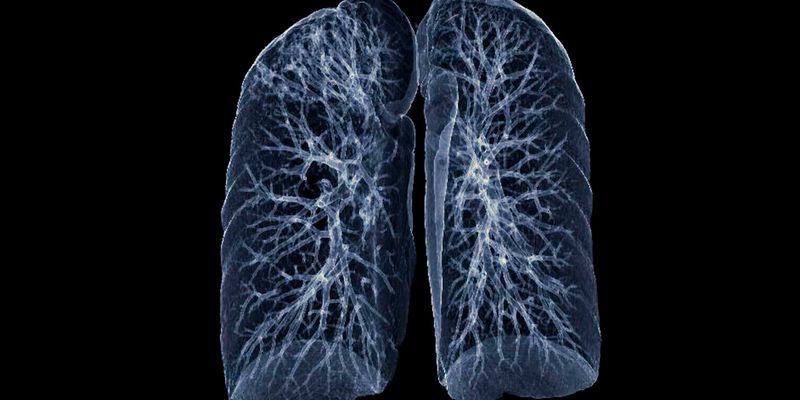

最新研究为多发性磨玻璃肺结节(GGO)患者带来新希望。研究表明,对于符合特定标准的低风险GGO,采取主动监测策略是安全有效的,5年总生存率高达100%,可避免不必要的手术和肺功能损伤。了解这一前沿诊疗策略,为您的健康做出更明智的决策。 Read More... "肺部磨玻璃结节一定要手术吗?最新研究证实:主动监测下5年生存率100%!"

最新研究表明,一项创新的多学科协作项目成功将肺癌筛查率从32.8%提升至71.6%,实现了翻倍增长。更重要的是,该项目使近八成(77.8%)的肺癌患者得以在早期阶段确诊,极大地提升了治疗成功率。如果您是高危人群,了解如何参与肺癌筛查至关重要。 Read More... "肺癌筛查率翻倍!新研究揭示多学科协作模式如何提高早期诊断率"

DUART研究显示,对于不适合化疗的III期非小细胞肺癌患者,度伐利尤单抗(Imfinzi)联合放疗展现出良好的疗效与可控的安全性。该方案显著延长了患者的无进展生存期和总生存期,为老年或体弱的NSCLC患者提供了一种全新的治疗选择。了解更多关于度伐利尤单抗的最新临床数据、副作用及购买渠道。 Read More... "无法化疗怎么办?度伐利尤单抗联合放疗治疗III期非小细胞肺癌疗效显著"

一项发表于《柳叶刀·肿瘤学》的回顾性研究显示,对于BRAF V600E突变的转移性非小细胞肺癌(NSCLC)患者,一线使用PD-1/PD-L1抑制剂(联合或不联合化疗)的中位总生存期显著优于BRAF/MEK抑制剂联合疗法(40.9个月 vs 25.2个月)。这一发现可能为该类患者的一线治疗选择提供新思路,了解更多治疗方案及药物获取途径。 Read More... "研究揭示:BRAF V600E突变非小细胞肺癌,一线免疫治疗生存获益超越靶向联合疗法"

最新研究揭示,肠道菌群或成预测局部晚期肺癌患者巩固免疫治疗效果及放化疗肺毒性的新关键。研究发现,基线肠道微生物多样性及特定菌群(如Akk菌)的动态变化,与患者的无进展生存期和严重肺炎风险密切相关。想了解如何优化您的治疗方案?点击探索更多前沿抗癌资讯。 Read More... "肺癌免疫治疗效果如何?Cell子刊重磅发现:肠道菌群是关键预测指标!"

EGFR突变肺腺癌患者免疫治疗效果为何不佳?本文特邀潘云建教授深入解读EGFR突变肺腺癌的免疫微环境特殊性,探讨其免疫逃逸机制与未来治疗新方向。文章还覆盖了肺磨玻璃结节的鉴别诊断与早期肺癌的微创治疗策略,为患者及家属提供全面的前沿抗癌资讯与治疗选择参考。 Read More... "专家解读:EGFR突变肺腺癌免疫治疗困境与未来出路"

颠覆传统认知!最新研究揭示,中国不吸烟女性的肺癌风险竟可能超过长期吸烟者。本文将深入剖析厨房油烟、空气污染、二手烟以及EGFR等关键基因突变如何成为隐形杀手,并提供低剂量CT筛查等实用预防策略。立即了解为何肺癌不再是吸烟者“专利”,为自己和家人的健康筑起防线。 Read More... "警惕!中国不吸烟女性肺癌高发,厨房油烟与EGFR突变是主因吗?"